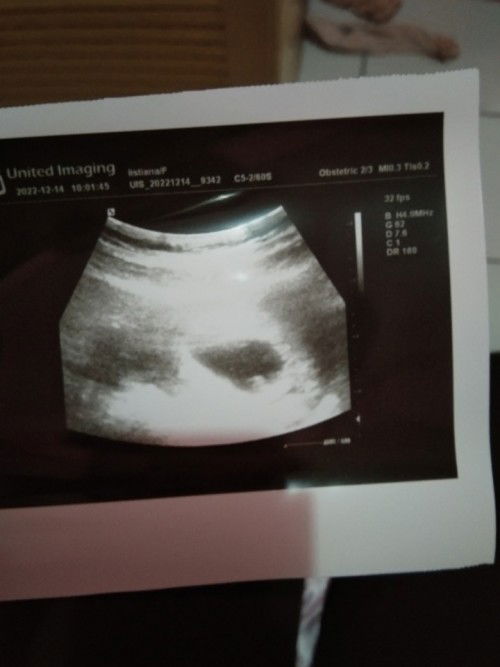

janin tidak berkembang ktnya suruh lngsung kuret , apa aku coba usg ke dr lain dulu ya bund

coba USG dr lain bun kalau ketauan hasilnya nanti gimanah share yah bun ku doakan Semoga bunda sehat wal'afiat dan dikaruniai calon buah hati

Baca lagicoba USG ke dr lain dulu bun